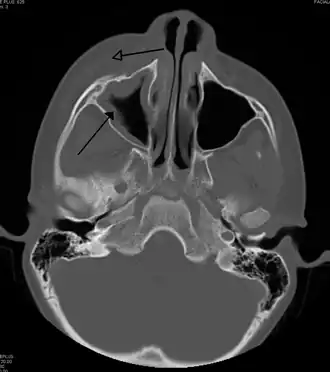

![]() Celulitis periorbitaria secundaria a infección dental (con presencia de sinusitis maxilar) | ||

Está producida por una infección, lesión o una picadura de un insecto. Los agentes más frecuentemente relacionados con este cuadro son el Saphylococcus aureus y el Streptoccoco pneumoniae. En los casos secundarios a sinusitis, puede existir presencia de Haemophilus influenzae (aunque con la vacuna del Haemophilus la celulitis periorbitaria secundaria a él, ha disminuido drásticamente)[3] u otros agentes. Puede ser causada secundariamente a alguna puerta de entrada local, como por ejemplo la picadura de un insecto o secundario a algún traumatismo en la región, además, también puede ocurrir debido a diseminación desde un foco contiguo, tal como se observa en las sinusitis o en las dacriocistitis.

La celulitis periorbitaria debe diferenciarse principalmente de la celulitis orbitaria, debido a que la segunda requiere un manejo hospitalizado con tratamiento antibiótico endovenoso y, en algunos casos, drenaje quirúrgico. En general, los pacientes con celulitis periorbitaria presentan una lesión eritematosa con bordes difusos, con aumento de la temperatura local, fiebre, dolor e inyección conjuntival con epífora. En contraste con una celulitis orbitaria, no tiene compromiso ocular (indemnidad de los movimientos oculares, ausencia de dolor y sin compromiso de la agudeza visual). En caso de presentarse alguno de estos síntomas, es necesario realizar una tomografía computarizada para descartar compromiso postseptal.[4]